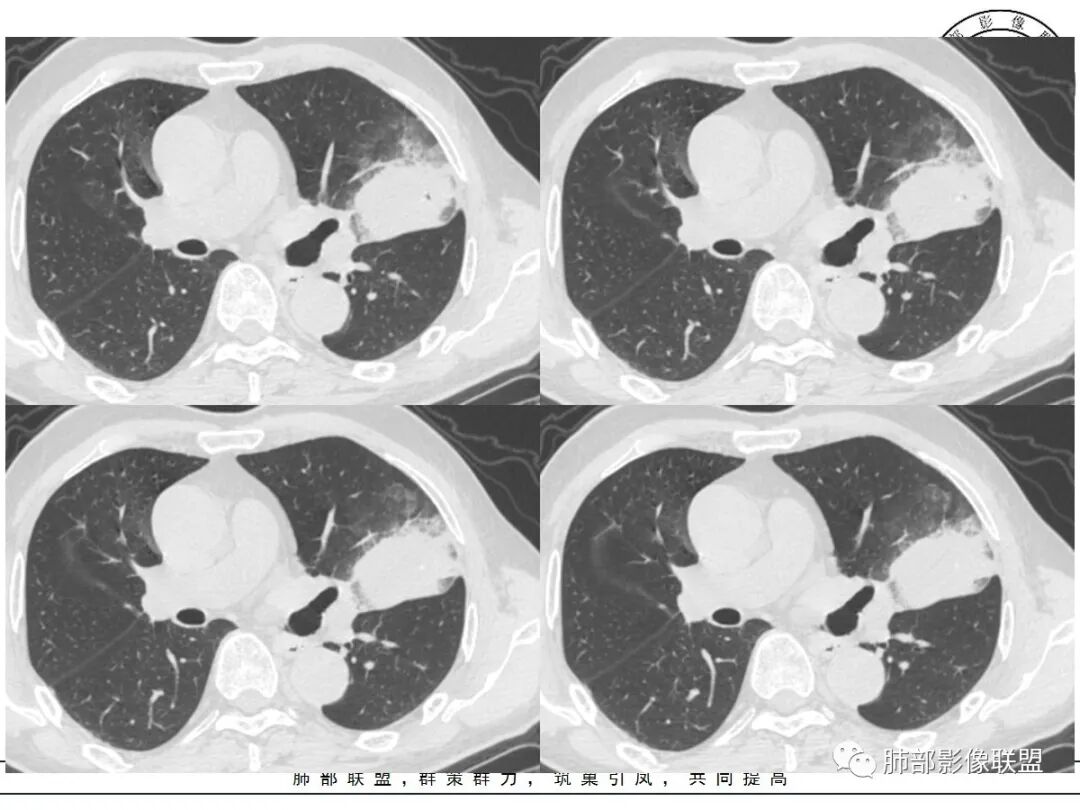

这三个月后的

发了后面这个,就不用纠结了,直接秒了。

我只是要告诉大家,不是二元,就是肿瘤,没有什么感染,磨玻璃都没消失。

@小赵 这个不一定是粘液,很可能还是周围癌性浸润。看术前复查,原磨玻璃区呈明显小叶间隔增厚改变了。说明还是癌性淋巴浸润。

@温附一影像科,傅钢泽 应该是STA(气腔播散)加癌性淋巴管炎。

1、团片状,实行密度区外观整体圆顿,位于上叶尖后段与下舌段区间。局部膨隆,但未见分叶,肿瘤多见。

2、偏心空腔病灶,气腔略呈新月形,壁不规则,腔内结节相对密实,明显强化且不均,支持新生物而非曲菌球等。炎性空洞多有强化环。

3、病变强化较明显,其内隐约显示多发小斑片状无强化灶,可疑边界不清小灶坏死区。病灶内血管影浅淡、模糊不规则。

4、支气管改变:上舌段支气管远段延入部分稍示僵硬。尖后段见分支支气管阻塞,恶性多见。

5、周围磨玻璃,3个月后逐渐转为密实,应符合当初附壁生长为主,且逐渐向实体成分转换。

6、病变长轴平行且受限于胸膜,外围大内带小,符合外朝内发展病变。“腔内结节状明显强化”加之支气管改变有力支持新生物诊断。如此大范围边界不清的磨玻璃影让人浮想联翩。如此大范围病灶,肺门纵隔未见肿大淋巴结也让人意外。